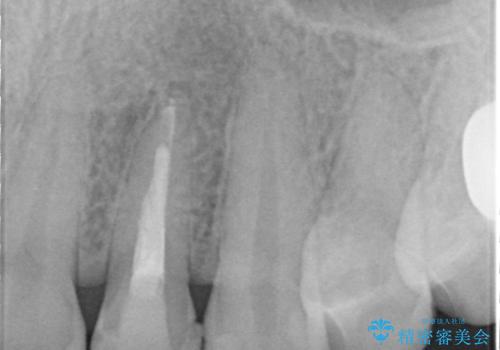

- 食べ物が歯間にはさまることを主訴に来院された患者様です。レントゲンより上顎両側切歯に根管治療が実施されていますが、被せ物が入っておらず、充填物に劣化像もみられました。歯の色の差も気にされていたのでオールセラミッククラウンにて治療いたしました。